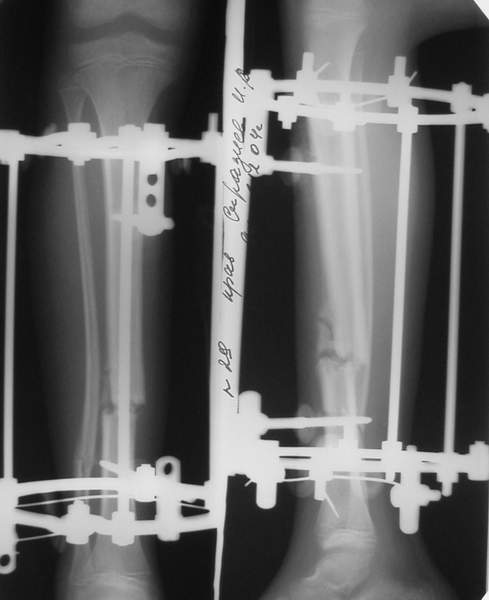

В аттачтах №№ 1 и 2 - примеры, когда 2 кольца не позволили послеоперационно

исправить смещение фрагментов большеберцовой (по ширине и вальгусное).

А казалось бы (#2) - поиграй на штангах и все влетит.

2